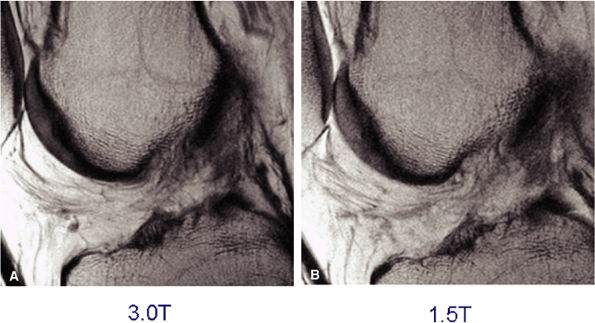

![]() |

|

FIGURE 1.32 ● Sagittal proton density-weighted images of the knee acquired with identical parameters at 3 T and 1.5 T. Note the improved SNR of the 3 T image (A) versus the 1.5-T image (B).